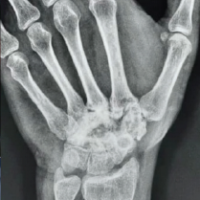

X-rays of the pelvis with both hips-anteroposterior view (Fig. 1) showed proximal and lateral migration of the proximal femur on the right side with an antibiotic nail in situ. A computed tomography (CT) scan was done to delineate the anatomy of the acetabulum and femur (Fig. 2).

Figure 2: Computed tomography scan (right hip joint).